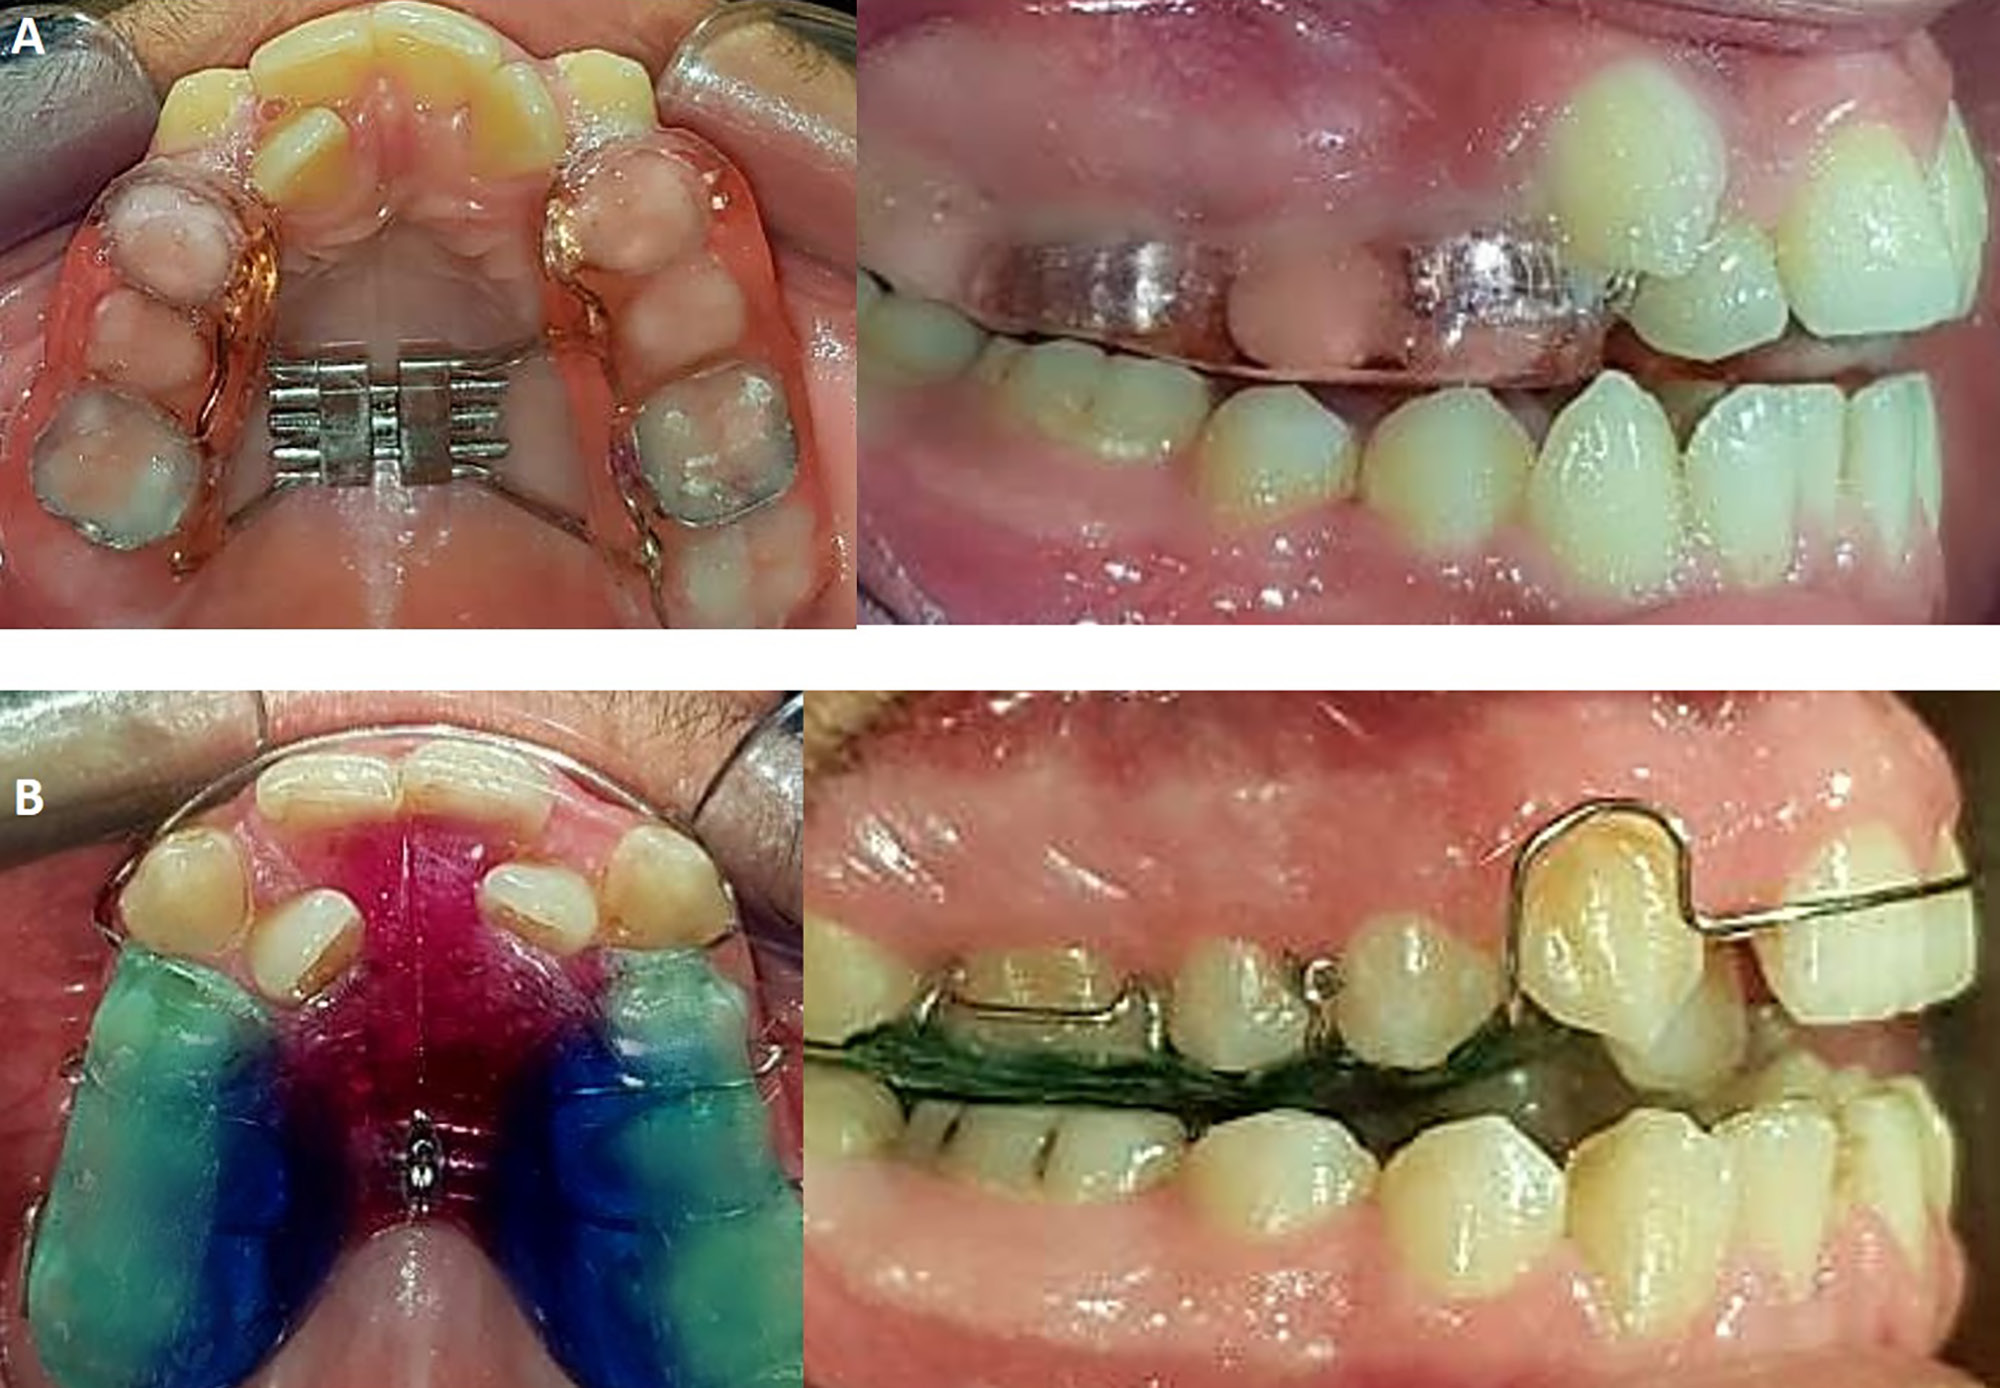

RME group and the activation protocol

The RME expander used in the current study was a modified Hyrax bonded rapid palatal expander with occlusal splints. Bonding was accomplished by using a conventional glass-ionomer cement (GIC) (Ketac™ Cem; 3M ESPE, Seefeld, Germany) on first premolars and first molars (Figure 2A). The patient activated the expander twice daily (these 2 movements produced half of a full screw turn, equivalent to 0.4 mm),13 until an overcorrection of maxillary constriction of approx. 2–3 mm was obtained.14 The expander was left in its place for 3 months as a retention period,15 and then, after removing the appliance, a CBCT image was taken.

SME group and the activation protocol

The SME expander used in the current study was a removable palatal expansion appliance consisting of posterior bite planes and a midline split incorporating 1 expansion screw (Figure 2B). The patient activated the expander twice weekly,13 until an overcorrection of maxillary constriction of approx. 2–3 mm was achieved.14 The expander was left in its place for 1 month as a retention period,5 and then, after removing the appliance, a CBCT image was taken.